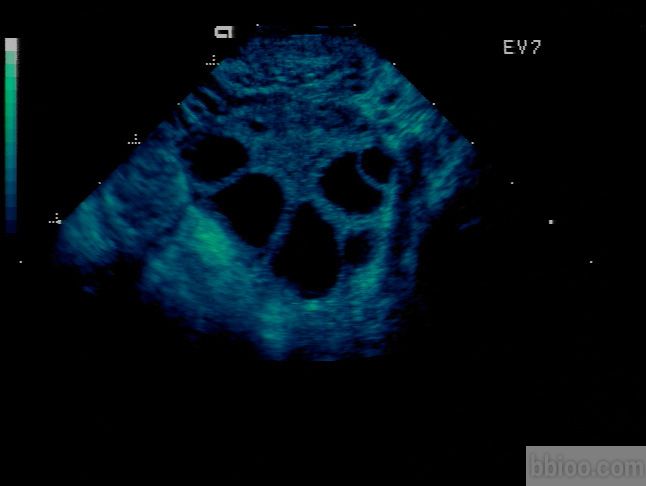

卵巢最主要的功能就是产生卵子,卵子在卵泡李和卵泡同步成熟,优生优育的基础就是发育良好的卵子。但是卵子太小,肉眼不可见,只能间接的通过观察卵泡来推测卵子的发育情况。B超检查是最直观最简单的评估办法,每个周期通过3~4次的阴道B超监测,可以观察到有没有正常的卵泡生长、发育、排出。

卵泡的大小在一定程度上反映出卵子的发育程度,可以用来预测排卵期以及最后的受孕几率。但是,我们能看到的仅仅是卵泡而不是卵泡当中包含着的卵子。成熟卵泡的直径是17~24mm,而卵子的直径在0.2mm左右,超声上是无法发现的。因此卵泡的大小并不能完全代表卵子的发育程度。在某些情况中,卵泡里面没有卵子,可能是因为卵子发育退化,也可能是先天的缺陷所致。

卵泡

受孕本身是一个复杂的过程,一个质量好的卵泡是好孕的首要条件。通过B超监测和激素的测定可以观察卵泡的发育情况,在医生的指导下增加受孕的机率。